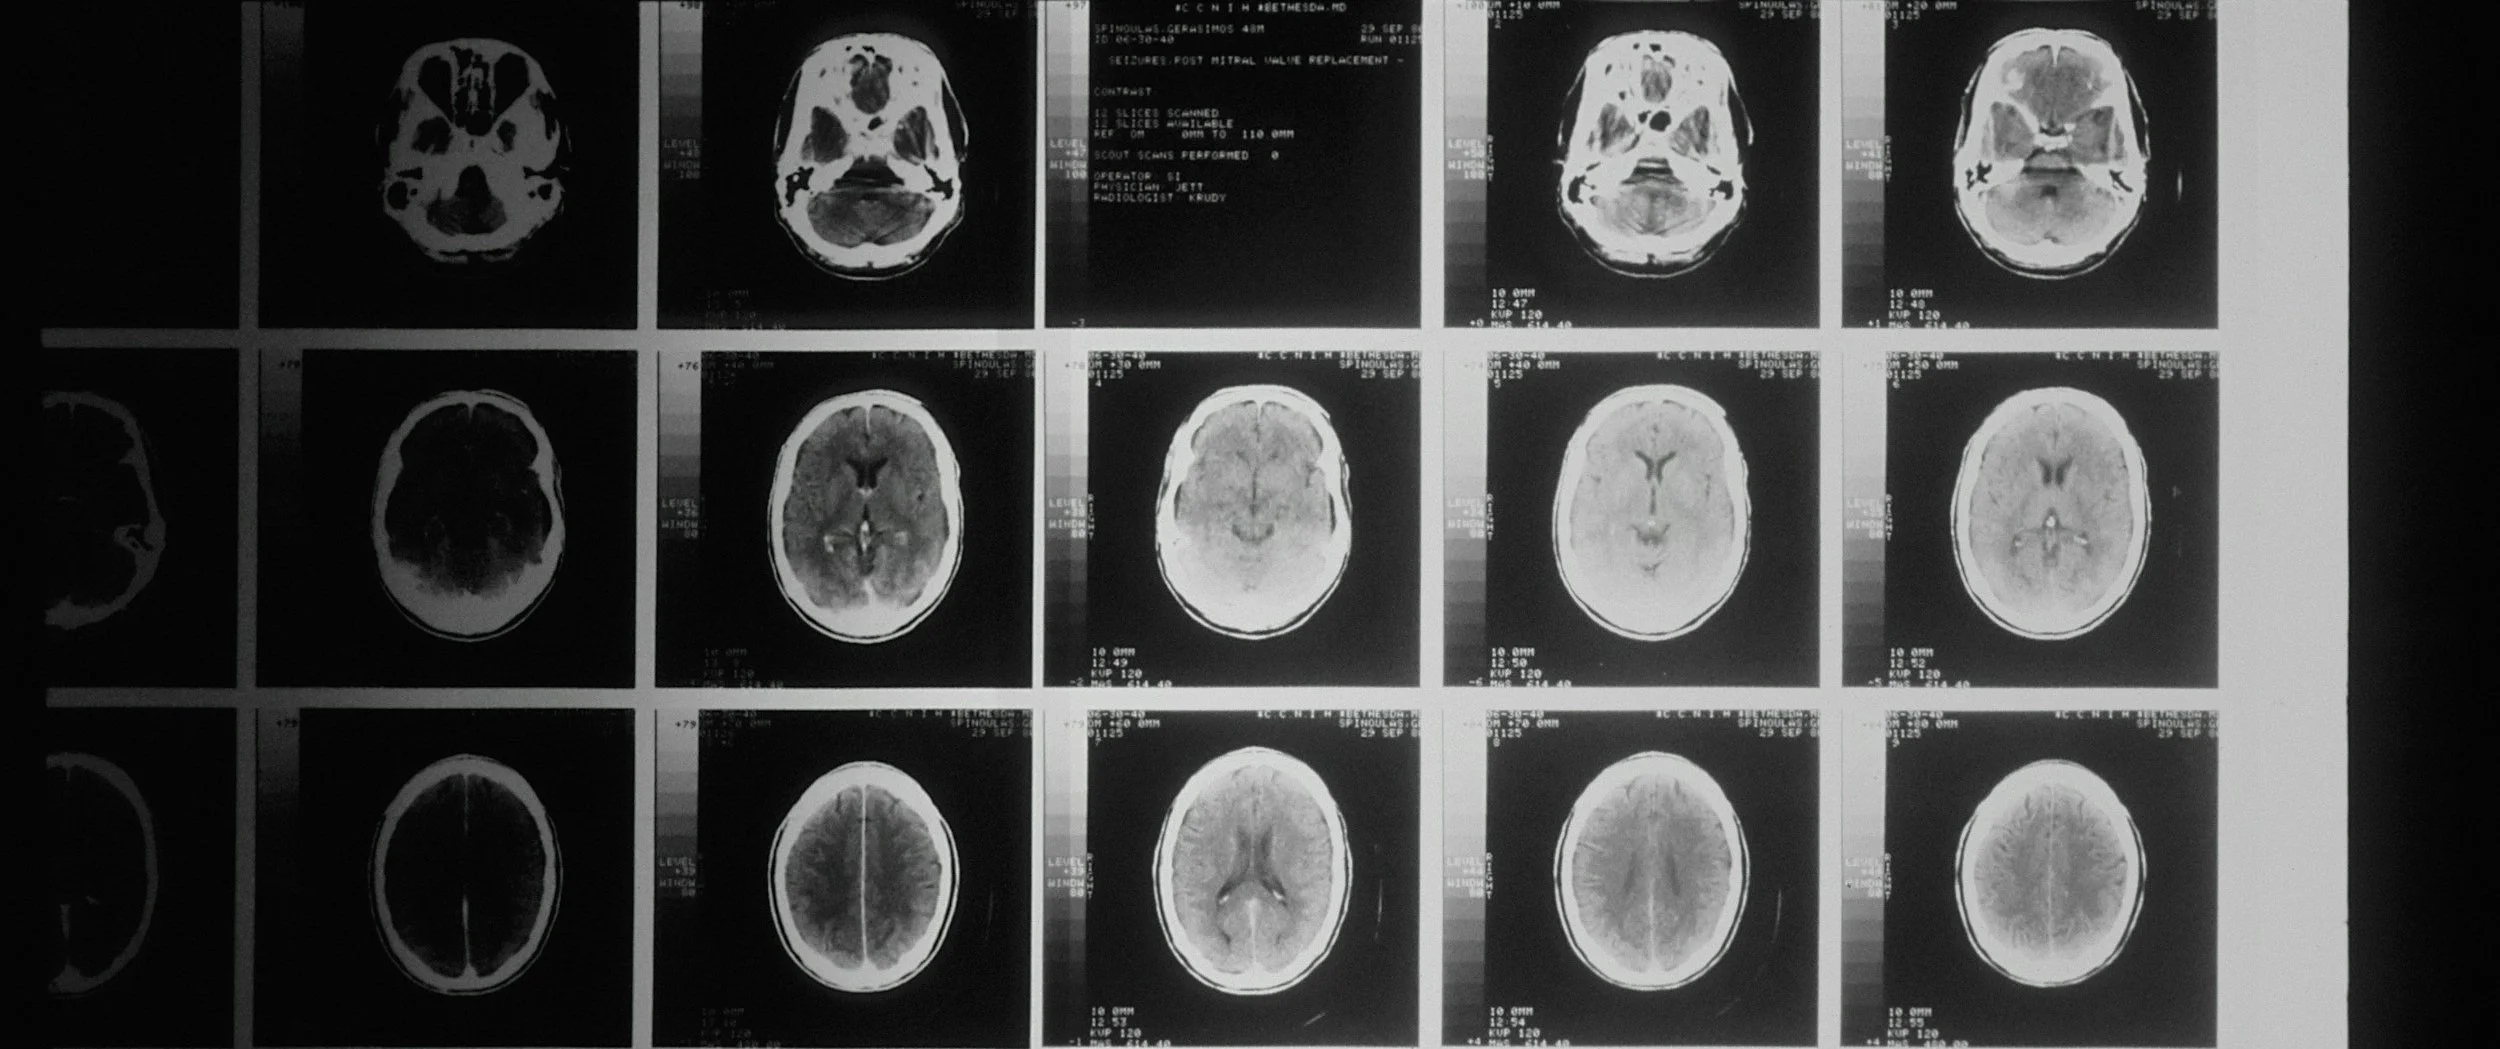

Neuroimaging Findings + Brain Efficiency

Functional MRI scans revealed that gamers’ brains exhibited higher activity in regions tied to attention and memory, and greater frontal lobe engagement during demanding tasks. Interestingly, areas responsible for basic visual processing were less active—suggesting that repeated visual challenges in gaming may foster neural efficiency, freeing up cognitive resources for complex problem-solving.